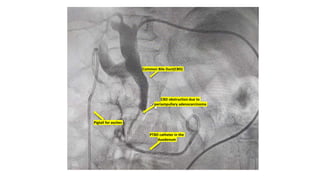

The document details a series of vascular procedures, including recanalization of the peroneal artery, medial plantar artery, and right brachiocephalic vein following occlusions. It also mentions angioplasty and the presence of abnormal blood flow in various uterine and bronchial arteries, along with complications like CBD obstruction due to a periampullary adenocarcinoma. Additional notes on venous collaterals and their disappearance are included.